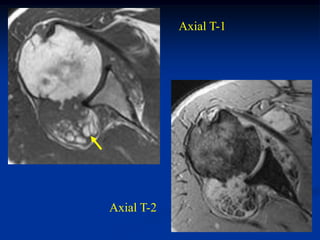

Case #1202

80 year male with

pleomorphic liposarcoma

Sagittal T-1 MRI

Sagittal T-2 MRI

Case #1202 80 yearmale with pleomorphic liposarcoma Sagittal T-1 MRI

• 255.